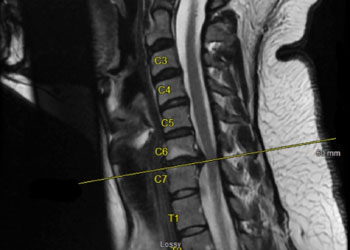

Spine:

Central Cord Syndrome

Author: Yusef Imani M.D., F.A.A.N.S., Read More!